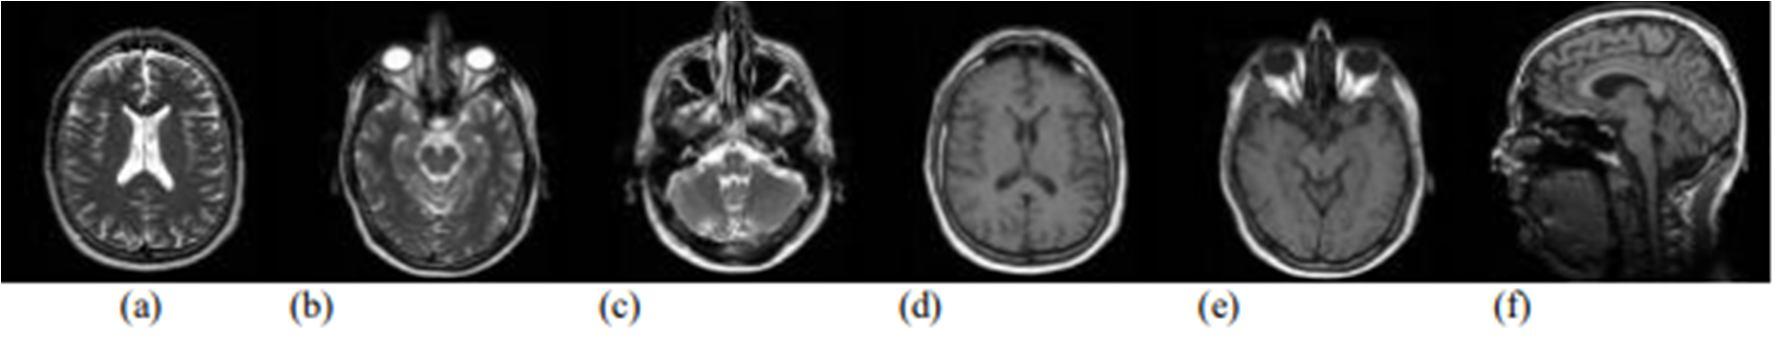

Figure 1: A set of brain tumor images from MRI of brain output cited

et al.(2003)[7]. a) Axial T1-weighted with tumor, b) T2-weighted with central positioning tumor, c) Contrast enhanced T1-weighted image showing ring formed tumor, d) Contrast enhanced T1- weighted image with high grade oligodendro glioma e) T2-weighted image with high grade oligodendro glioma from the same patient.